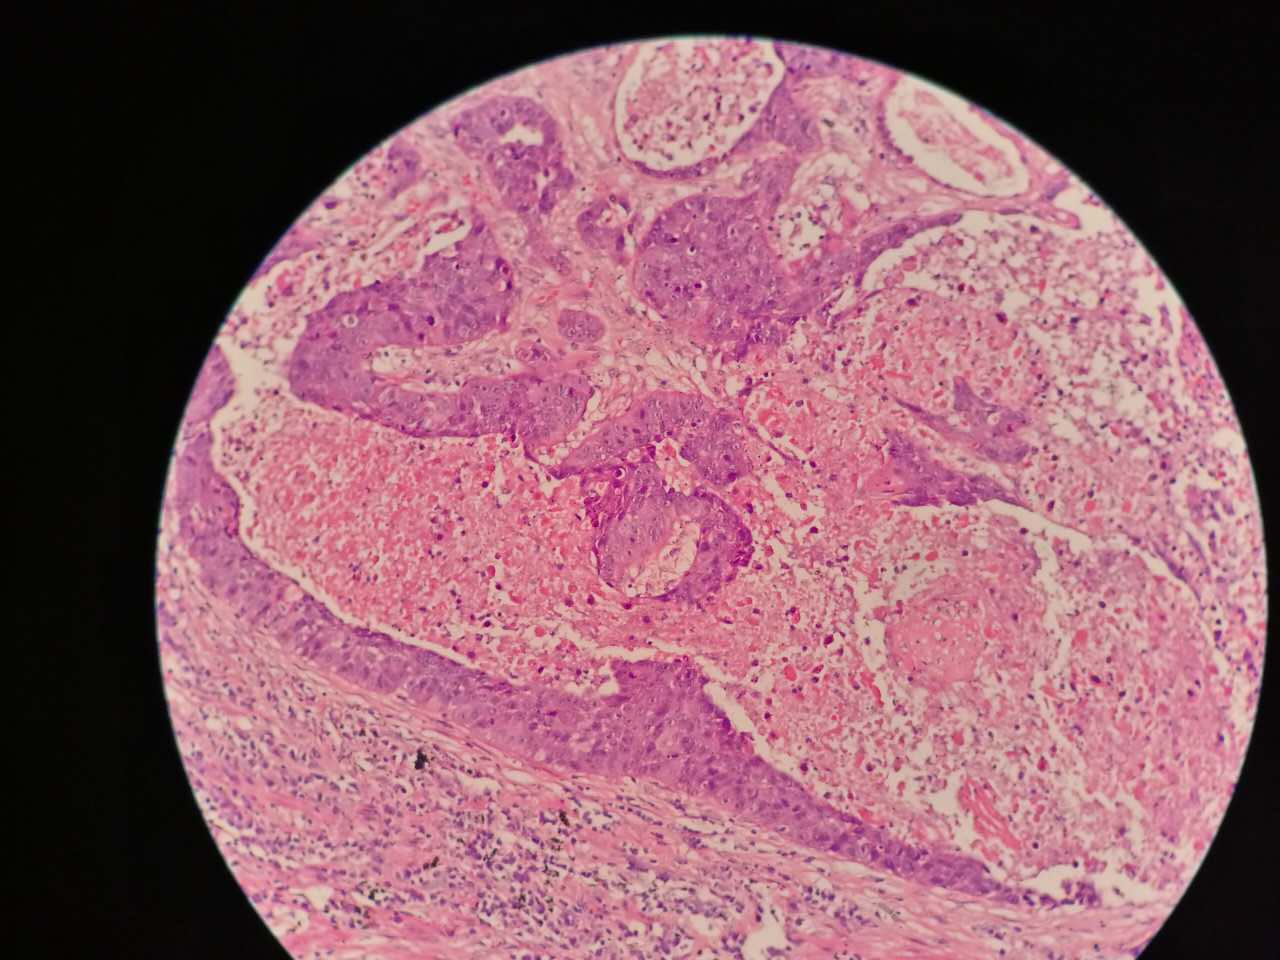

鳞癌生长,呈巢团状

巢团边界大多清楚

巢团可以很大,中央血供不足,就会坏死

中央红色的,有碎核

这个鳞癌不是早期

坏死也可以很大

较大的粉红区都是坏死,可以看出坏死是因为巢团大,中央坏死

一侧常有突起,也就是壁结节。

壁结节不必等到空洞形成才判断,有坏死区就可以在增强片上判断有无壁结节

这个中央那块也算是小型的壁结节,肿瘤组织突入坏死区。或者说,这块肿瘤组织没坏死。